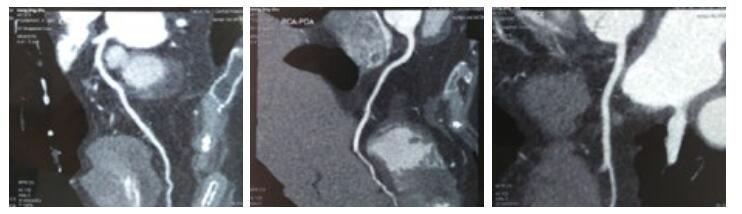

第1天,心脏超声提示:左房38 mm,左室舒张末内径50 mm,射血分数50%。左室下壁后壁运动减低,左室收缩功能减低,心律失常,二、三尖瓣轻度反流。血化验回报:血常规:白细胞(WBC)15.32×109/L,中性粒细胞(NEUT)比例55.64%,嗜酸性粒细胞(Eosinophil,EO)比例18.81%(绝对值2.88×109/L)。入院后给予左西孟旦等药物对症治疗。第3天,血常规回报:WBC 13.07×109/L,NEUT比例44.0%,EO比例42.0%(绝对值5.49×109/L)。第4天,复查血常规回报:WBC 12.6×109/L,NEUT比例43.6%,EO比例36.9%(绝对值4.6×109/L),复查cTnT 4.16 ng/mL;NT-proBNP 13 840 pg/mL。患者症状略缓解。追问病史:入院前1年曾3次就诊于外院,且反复多次出现EO异常升高,最高2.32×109/L,动态对比胸部CT情况可见游走性斑片影,且入院前1周行冠脉CTA检查未见异常。故考虑Löffler心内膜炎可能。第5天,给予甲强龙40 mg静脉,第6天复查血常规WBC 7.2×109/L,NEUT比例87.2%,EO比例0.5%(绝对值0.0×109/L)。持续给予甲强龙40 mg静脉5 d,第10天复查血常规WBC 9.5×109/L,NEUT比例70.1%,EO比例0.7%(绝对值0.1×109/L);cTnT 2.24 ng/mL;NT-proBNP 6 481 pg/mL,住院期间查ANCA阴性,曲真菌抗体阴性、C反应蛋白、降钙素原、体液免疫、风湿全项均正常。入院后11 d症状好转出院。

| 图 1 入院前1周冠脉CTA情况(A前降支;B右冠;C回旋支) |

患者因心前区不适入院。急诊查cTnT及NT-proBNP明显异常,提示心肌损伤、心功能不全诊断明确。但入院后反复复查血常规,EO均明显升高,且患者入院前1周行冠脉CTA未见异常,加之入院后心肌酶、心电图不符合AMI动态演变过程。另外患者1年内多次入院均出现EO均异常升高(均大于 > 1.5×109/L),提示存在嗜酸性粒细胞增多症,胸部CT可见游走性斑片影,提示存在嗜酸性粒细胞增多综合征[1]。尽管未做心肌活检,但患者具有心血管系统、呼吸系统损害,EO计数反复大于 > 1.5×109/L,故笔者认为Löffler心内膜炎诊断明确。